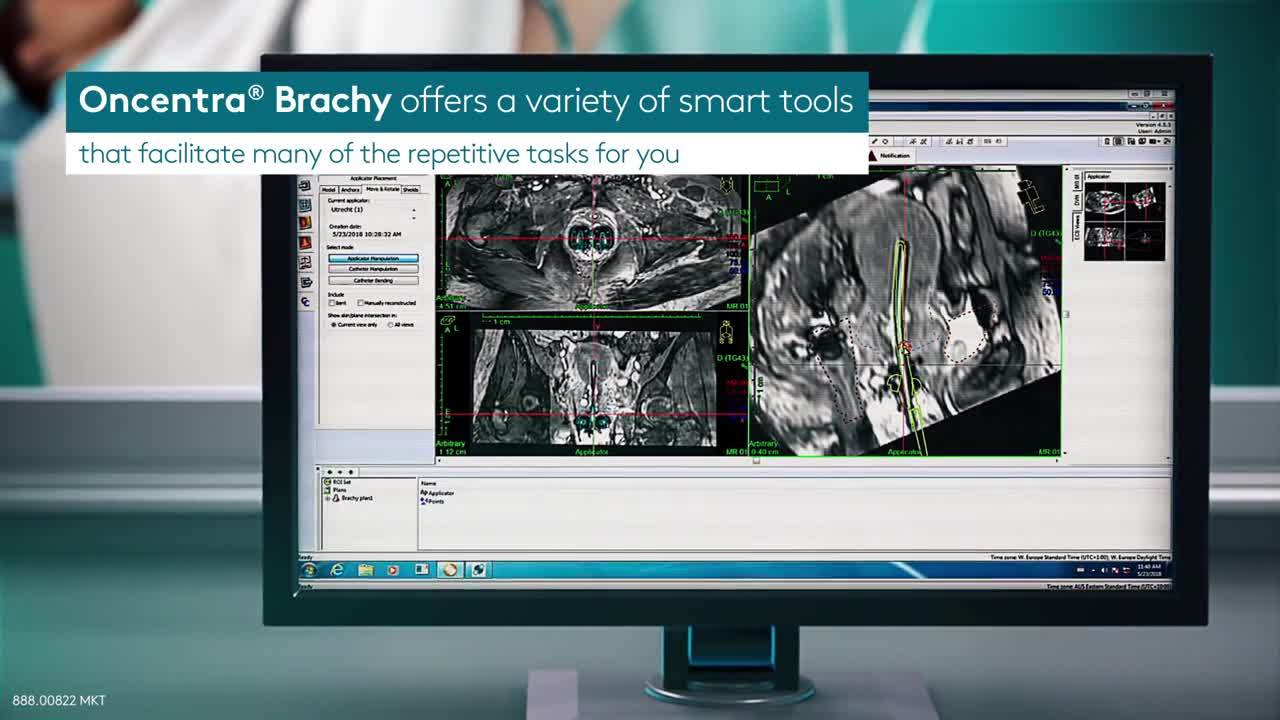

优化剂量分布的设计工作非常耗时。最新版Oncentra Brachy提供了一系列实用工具,可帮助简化许多重复性任务,例如勾画和重建。Oncentra Brachy让您能够节省时间,集中精力来确定最佳的剂量分布。